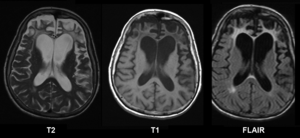

| Brain MRI in Pick's disease | |